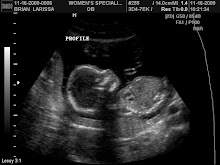

It was confirmed today. Olivia Grace has Trisomy 18. This diagnosis is a fatal chromosone disorder. The chances of survival are very slim.